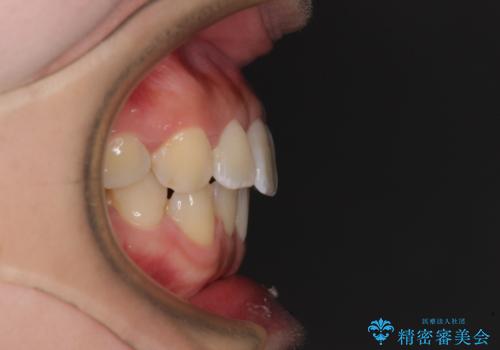

- 上顎歯列と下顎前歯の叢生を気にして来院された患者様です。

上顎からワイヤー矯正を開始し、終了間際から下顎前歯の叢生解消するよう計画しました。

部分矯正でしたが、咬み合わせに違和感が出ることなく気になる部分を改善させることができました。